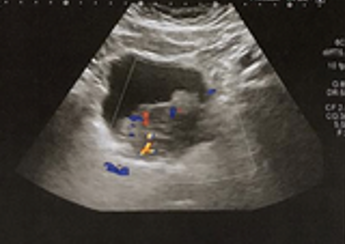

- USG – dilatação bilateral, massa vesical

- Nefrostomia direita com punção guida por USG